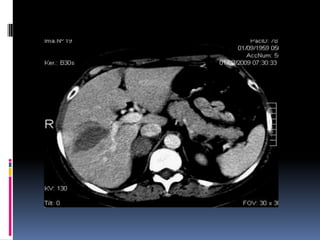

 Segundo órganomas afectado  Lesiones similares a las hepáticas  Sospecha de lesión:  Contornos borrosos  Líquido espacio pararrenal anterior y lateroconal izquierdos  Coágulo centinela

 Pitfalls:  Hendiduras (cleft) congénitos  Artificios de costillas, interfases aire-líquido (estómago, intestino), sondas o catéteres metálicos  Heterogeneidad fase arterial